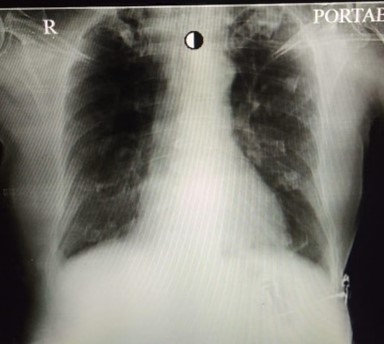

Mr M, 78 years was admitted under my care for the treatment of severe COVID 19. His oxygen level was very low on admission. If left unsupported, he would worsen dangerously. He needed high quantity of oxygen with special type of mask. His condition remained same for next two days. However on the evening of the third day I found him breathing rapidly. He complained that he spit blood in sputum so all forms of blood thinning medicines were stopped. Theses medicines are given to patients of severe COVID to prevent unwanted blood clotting. Late evening he complained of difficulty in breathing. On examination he was distressed. He was given non-invasive ventilator i.e. ventilator support with mask but he could tolerate it for few hours nothing was working for him. His condition deteriorated further with severe distress and mismatch with ventilator leading to fall in oxygen levels. I intubated i.e. inserted a tube in his wind pipe and kept him on ventilator. His X ray chest showed extensive shadows covering almost two third of the lung fields. COVID had badly affected his lungs and it was impossible for him to breathe on his own. He was managed with ventilator. His lungs were very stiff. For next three to four days he remained critical. However as the days passed his lung compliance improved. His X ray chest showed remarkable improvement. His ventilator support was reduced. He was given a challenge of self-breathing a day after his parameters improved. He did well and the tube that was kept in his wind pipe through his mouth for providing mechanical ventilator support was taken out. Now he was able to breathe on his own i.e. without any artificial support. His condition kept improving thereafter. He recovered well and discharged from the hospital

BEFORE